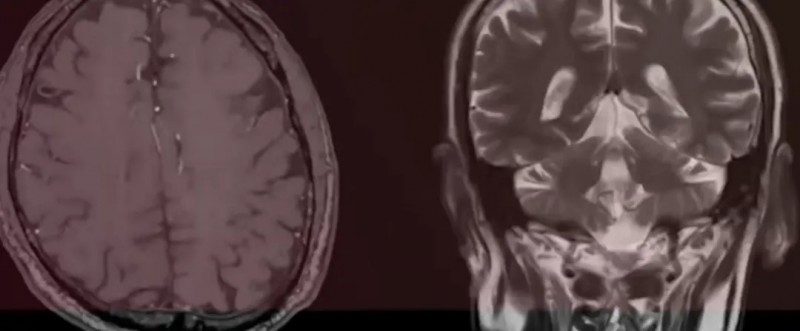

影像结果如晴天霹雳:莱昂的额叶过度发育,颅内肿瘤疯狂生长,头部肿胀得像“一头白鲸”,必须立刻手术!周二做检查,周三紧急动身术前准备,夫妻俩被卷入医疗决策的旋风,连悲伤的时间都没有。“我们根本来不及思考,只能跟着医生的脚步跑,心里只有一个念头:救救我的孩子。”

紧急开颅手术过后,莱昂的情况雪上加霜:输血、静脉破裂、颅内严重肿胀,生命体征长时间不稳定,还接连做了两次分流手术,在重症监护室整整挣扎了两周。“护士告诉我们,莱昂的病例是她们见过最令人震惊的病例之一。”那段日子,医院的仪器滴答声是夫妻俩最恐惧的声音,孩子插满管子的小小身躯,成了他们心中永远的痛。更糟的是,术后的病理结果显示,莱昂的肿瘤竟是高级别星形细胞瘤——一种侵袭性极强的恶性脑癌,预后极差,莱昂的生命进入了倒计时。

抱着最后一丝希望,医生将莱昂的肿瘤组织送去做了全面的分子谱分析。但万幸的是,他的肿瘤中竟然检测出了非常罕见NTRK基因融合——这个结果意味着,他可以使用全球首款不限癌种,专门针对NTRK融合的靶向药——拉罗替尼。

如今的莱昂,已经两岁了,拉罗替尼成功稳定了他的颅内肿瘤,没有出现任何治疗相关副作用,那个爱笑的小天使,重新回到了他的生活里。